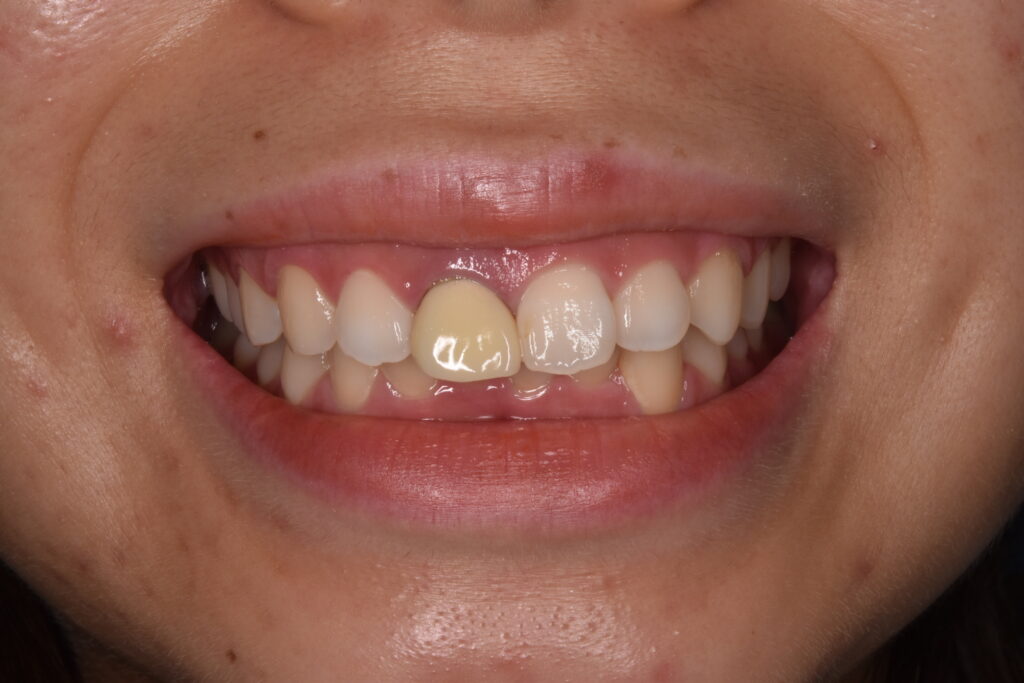

右の前歯の歯ぐきの黒ずみと古い被せ物のやりかえ治療をしています。歯の高さが左右で違うため歯肉整形をしています。*さくらセラミックプラン